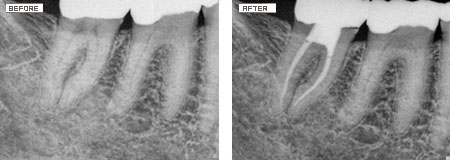

Root Canals